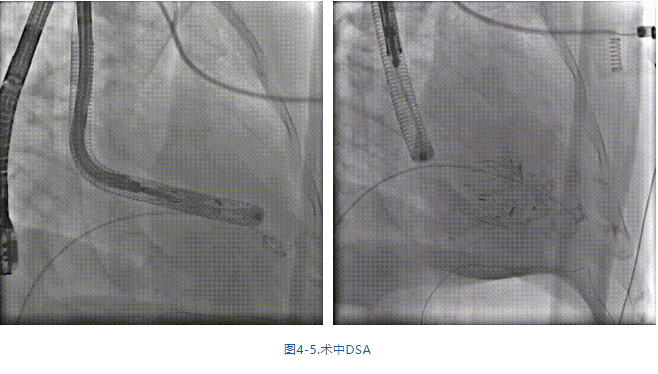

手術(shù)在全麻狀態(tài)下進行,采用經(jīng)右側(cè)頸靜脈入路,在TEE和DSA的指引下緩慢送入輸送器進入體內(nèi),進入右室后釋放室間隔錨定裝置,旋轉(zhuǎn)輸送器,使得錨定裝置對準(zhǔn)室間隔面;釋放前瓣夾持件,確定夾持件位于右室側(cè)后釋放人工瓣膜盤片,DSA及超聲確認(rèn)盤片位于右房側(cè),并適時調(diào)整瓣膜的同軸性。在DSA和超聲的監(jiān)視下調(diào)整室間隔錨定件貼合室間隔,釋放室間隔錨定裝置。再次確認(rèn)瓣膜的穩(wěn)定性和同軸性后,將輸送器撤出體內(nèi),最終完成瓣膜植入(圖4-5),手術(shù)室即刻拔除氣管插管。術(shù)后超聲提示人工三尖瓣同軸性良好,瓣架固定牢靠,無反流和瓣周漏,術(shù)后三尖瓣平均跨瓣壓差顯著降低。